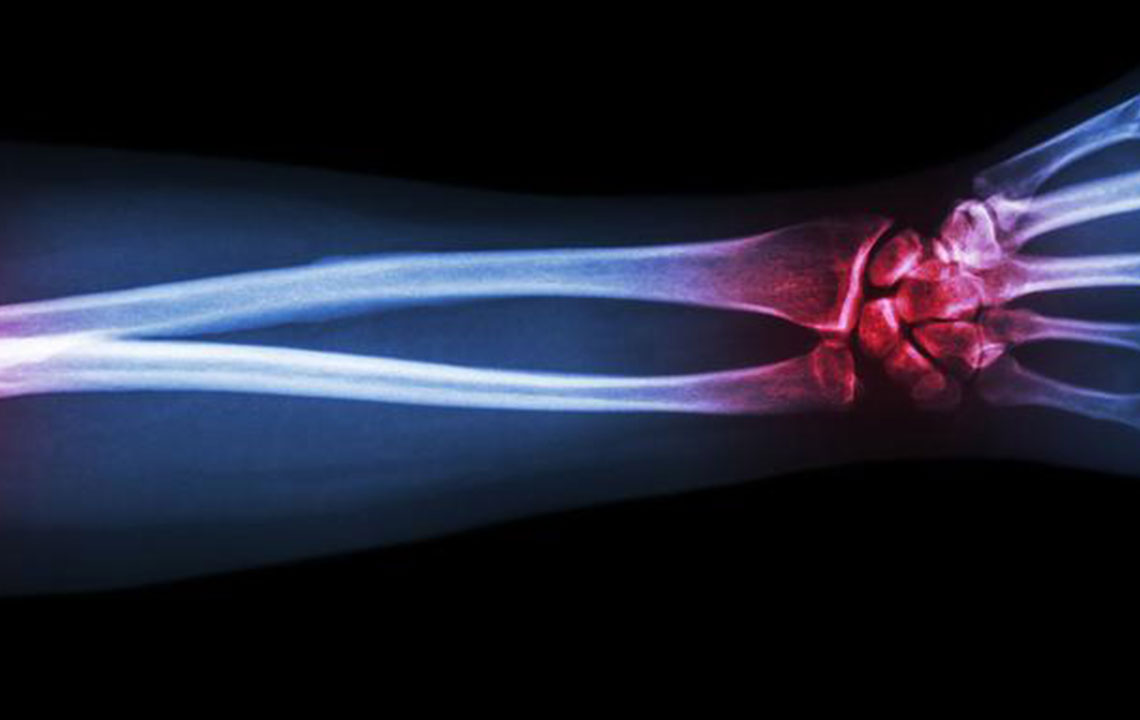

Gout is a type of arthritis that primarily attacks the joints and other body parts like the ears, wrists, knuckles, knee, ankles, and other small joints. It is often characterized by painful swelling, stiffness, and inflammation of these affected joints. The swelling and stiffness are mainly the results of excess levels of uric acid forming crystals in the joints. The pain is due to the inflammatory response to the crystals formed.

The causes of gout may include lack of exercise, high levels of uric acid in the system, genetics, excessive consumption of meat, being overweight, menopause, excessive consumption of alcohol, stress, and excessive protein content in the body. It mainly affects the big toe, causing an increased swelling, inflammation, and redness in the affected area.

The deposition of uric acid crystals in the joint causes inflammation and makes the movement of the joint agonizing. The elevated levels of uric acid in the system also causes the depositing of crystals in the kidney, which, in turn, leads to stone formation.